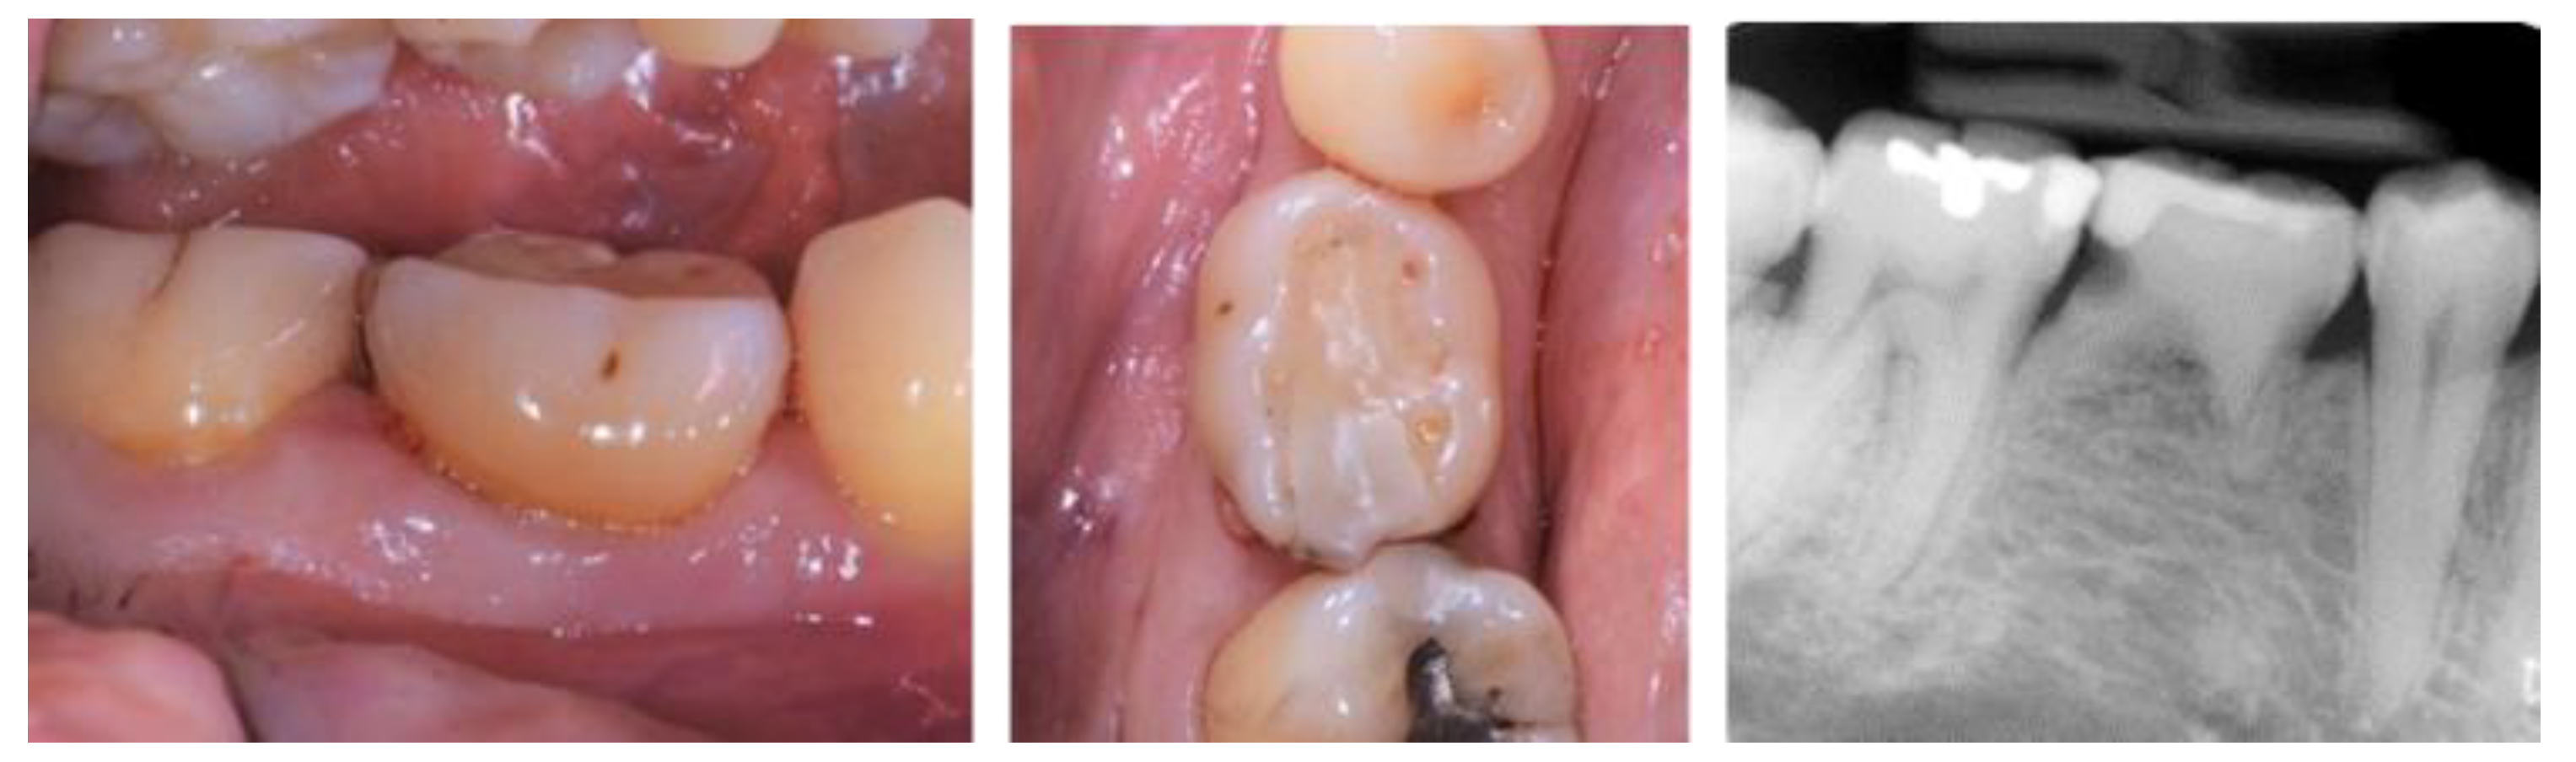

2.5. Individual Cases Description

- Case 1:

- Case 2:

- Case 3:

- Case 4:

- Case 5: